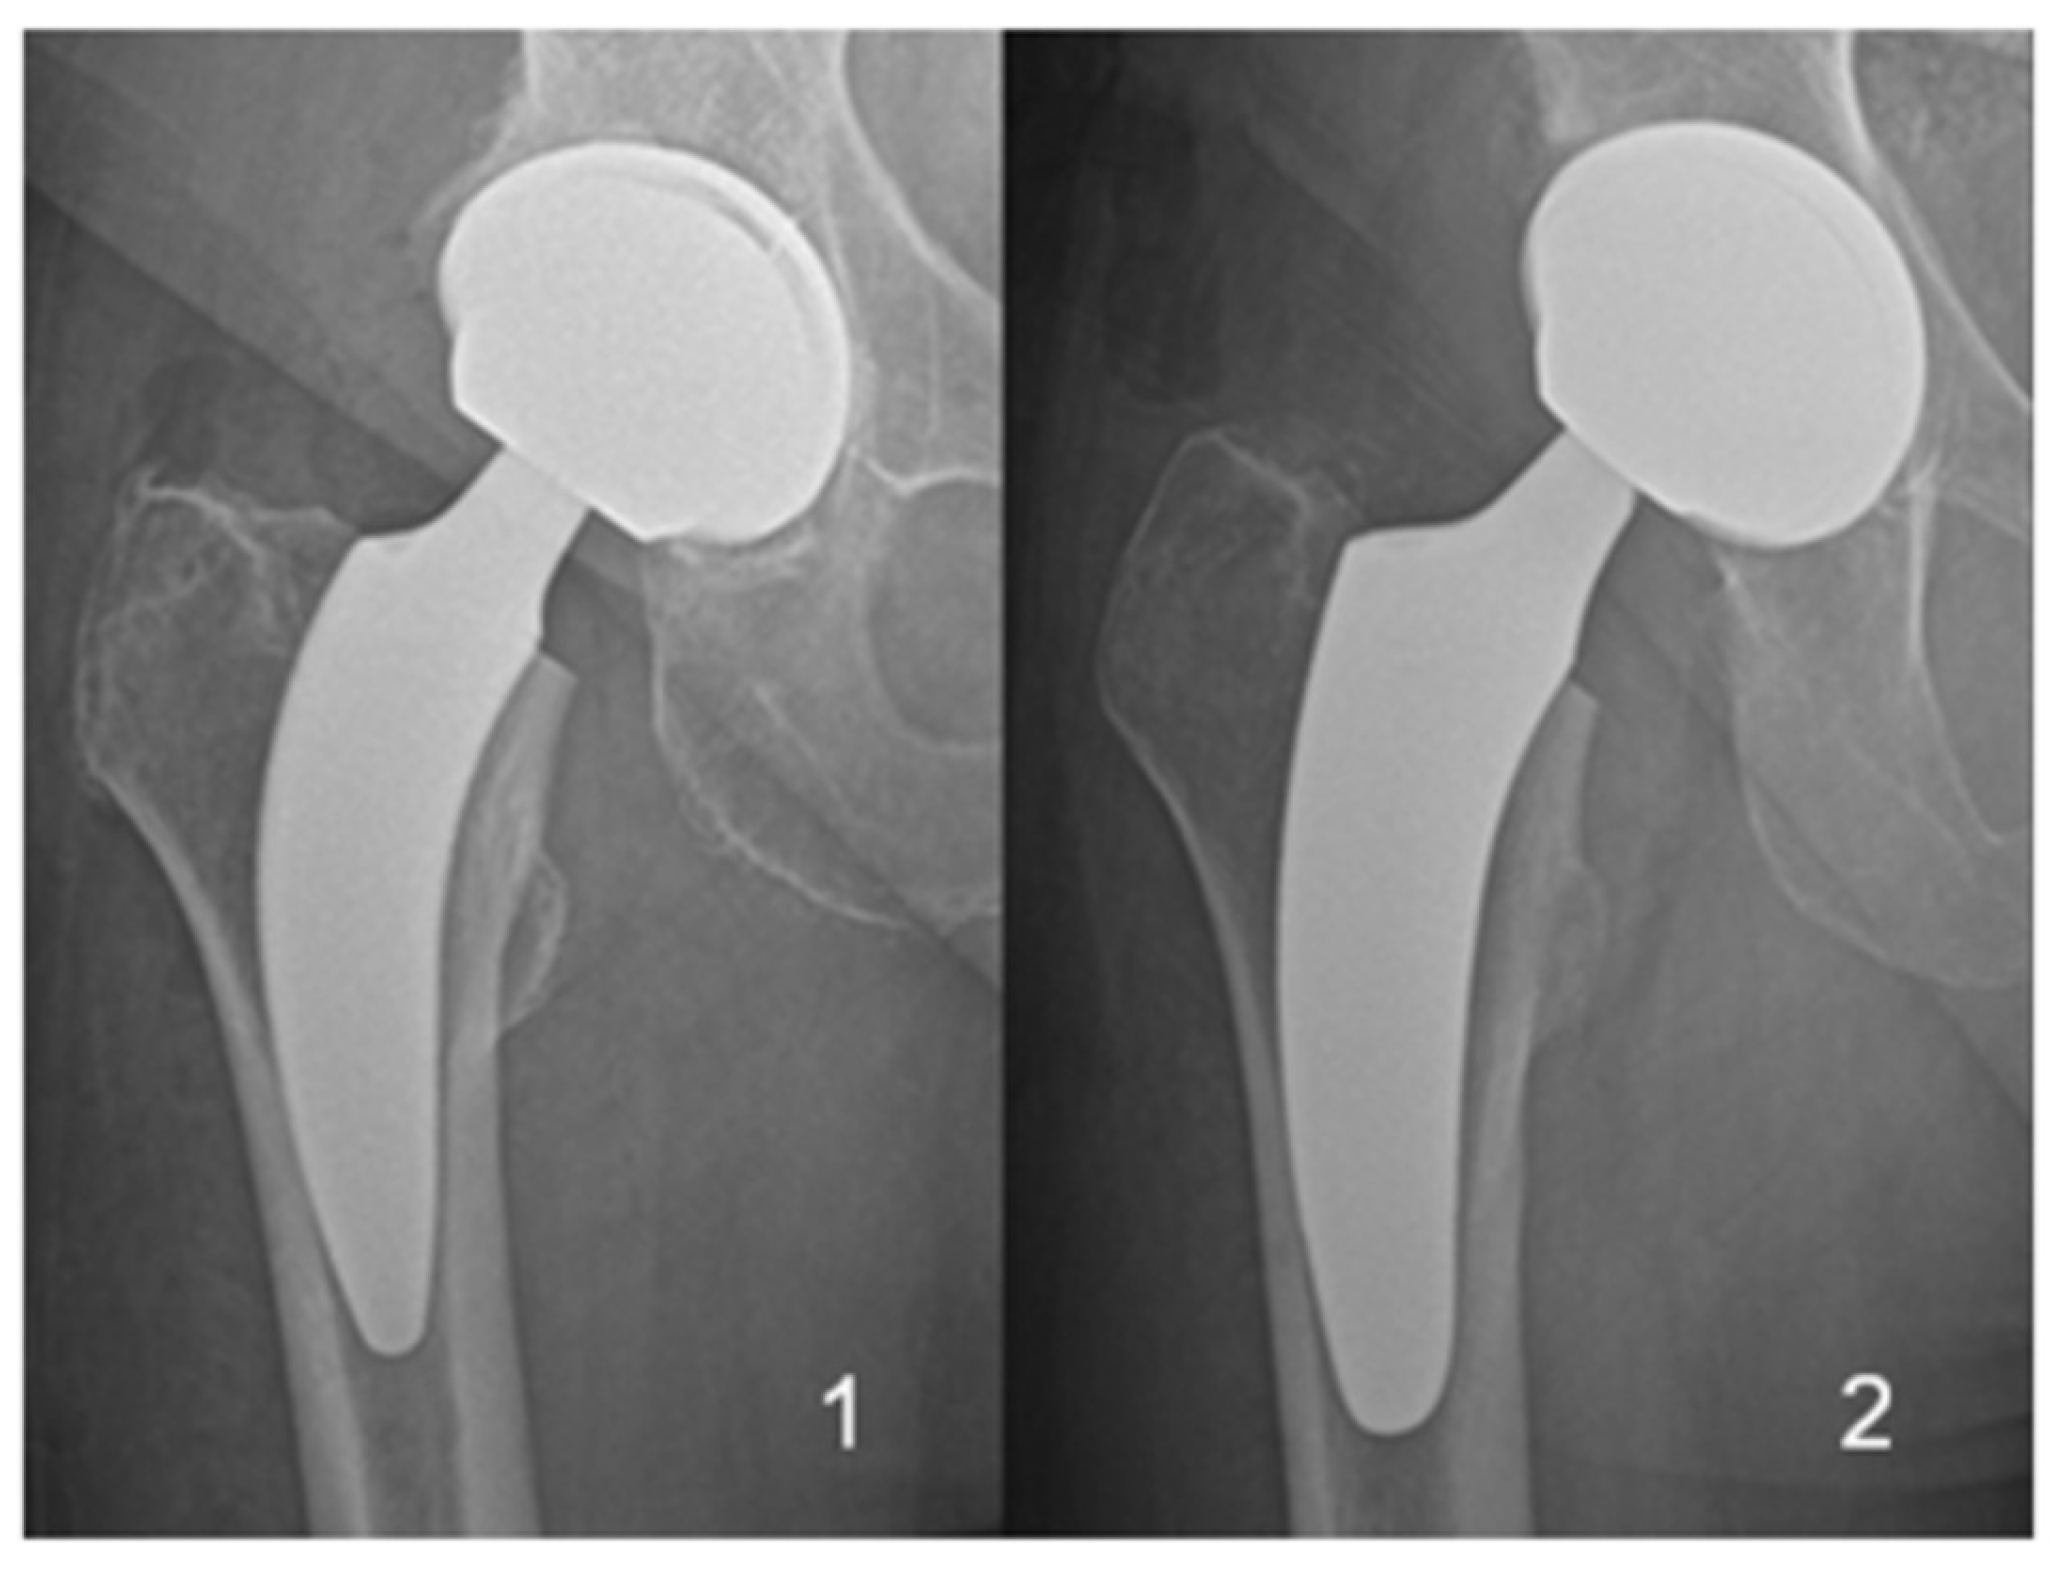

The two different short-stem designs with proximal metaphyseal fixation, which were implanted in all patients, are shown in Figure 1. Patients were stratified into two groups based on the implanted short-stem design.

(1)

ANA.NOVA Alpha stem proxy® (ImplanTec GmbH, Moedling, Austria)

(2)

Optimys® (Mathys AG, Bettlach, Switzerland)

In a total of 44 THAs, the Alpha Stem Proxy® was used, while in the other 71 THAs, the Optimys® stem was utilized.

Figure 1. Stems compared included the Alpha Stem proxy® (1) and Optimys® (2).